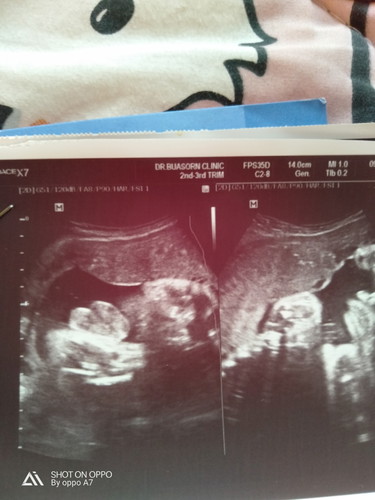

วันก่อนไปซาวคุณหมอบอกเป็นผู้ชายแม่ๆว่า ช หรือ ญ ค่ะ